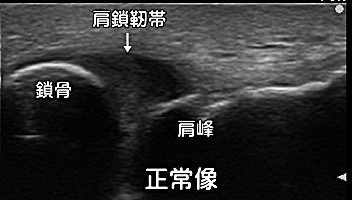

超音波診断②(靱帯損傷)

肩鎖関節靱帯損傷で靱帯損傷の見え方を説明します。正常の黒い均一な三角形の靱帯(下図)が幅広く大きく中にまだら状の白い部分見え(上図)損傷を来しています。